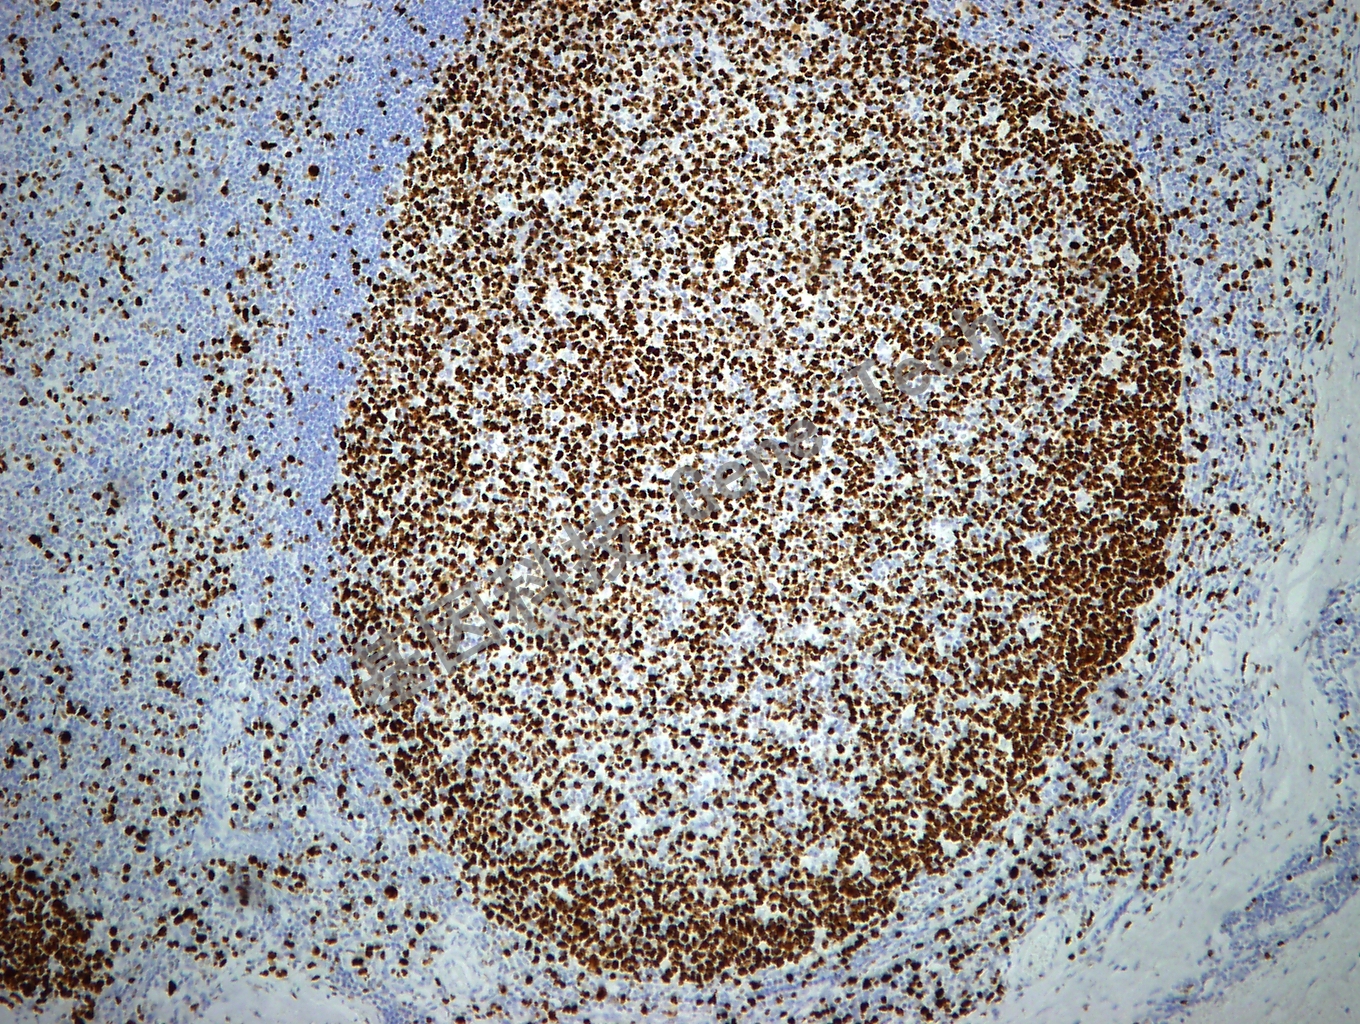

Ki-67 鼠抗人 Ki-67 抗體試劑(免疫組織化學(xué))(GM027)

| 克隆號(hào):GM027 | 種屬:鼠 | 適用染色系統(tǒng):GTvisionTM |

| 預(yù)處理:高pH熱修復(fù) | 陽性部位:細(xì)胞核 | 陽性對(duì)照:扁桃體 |

| 簡(jiǎn)介:Ki-67可以識(shí)別出在細(xì)胞增殖周期G1、S、G2和M期的細(xì)胞,而處在G0期的細(xì)胞不著色??膳袛嗉?xì)胞的增殖活性,是確定良惡性組織生長(zhǎng)狀態(tài)的標(biāo)記。研究表明,它與乳腺癌的組織學(xué)分型、核分裂指數(shù)和淋巴結(jié)轉(zhuǎn)移情況密切相關(guān),由于Ki-67比PCNA更為直接反應(yīng)細(xì)胞的增殖情況,因此常用于某些惡性腫瘤預(yù)后的一個(gè)重要參考指標(biāo)。有助于判斷淋巴瘤的惡性程度,高級(jí)別淋巴瘤Ki-67一般大于40%或50%。 | ||

| 扁桃體石蠟切片,用 Ki67(GT2094)染色,細(xì)胞核陽性,DAB 顯色。 | ||